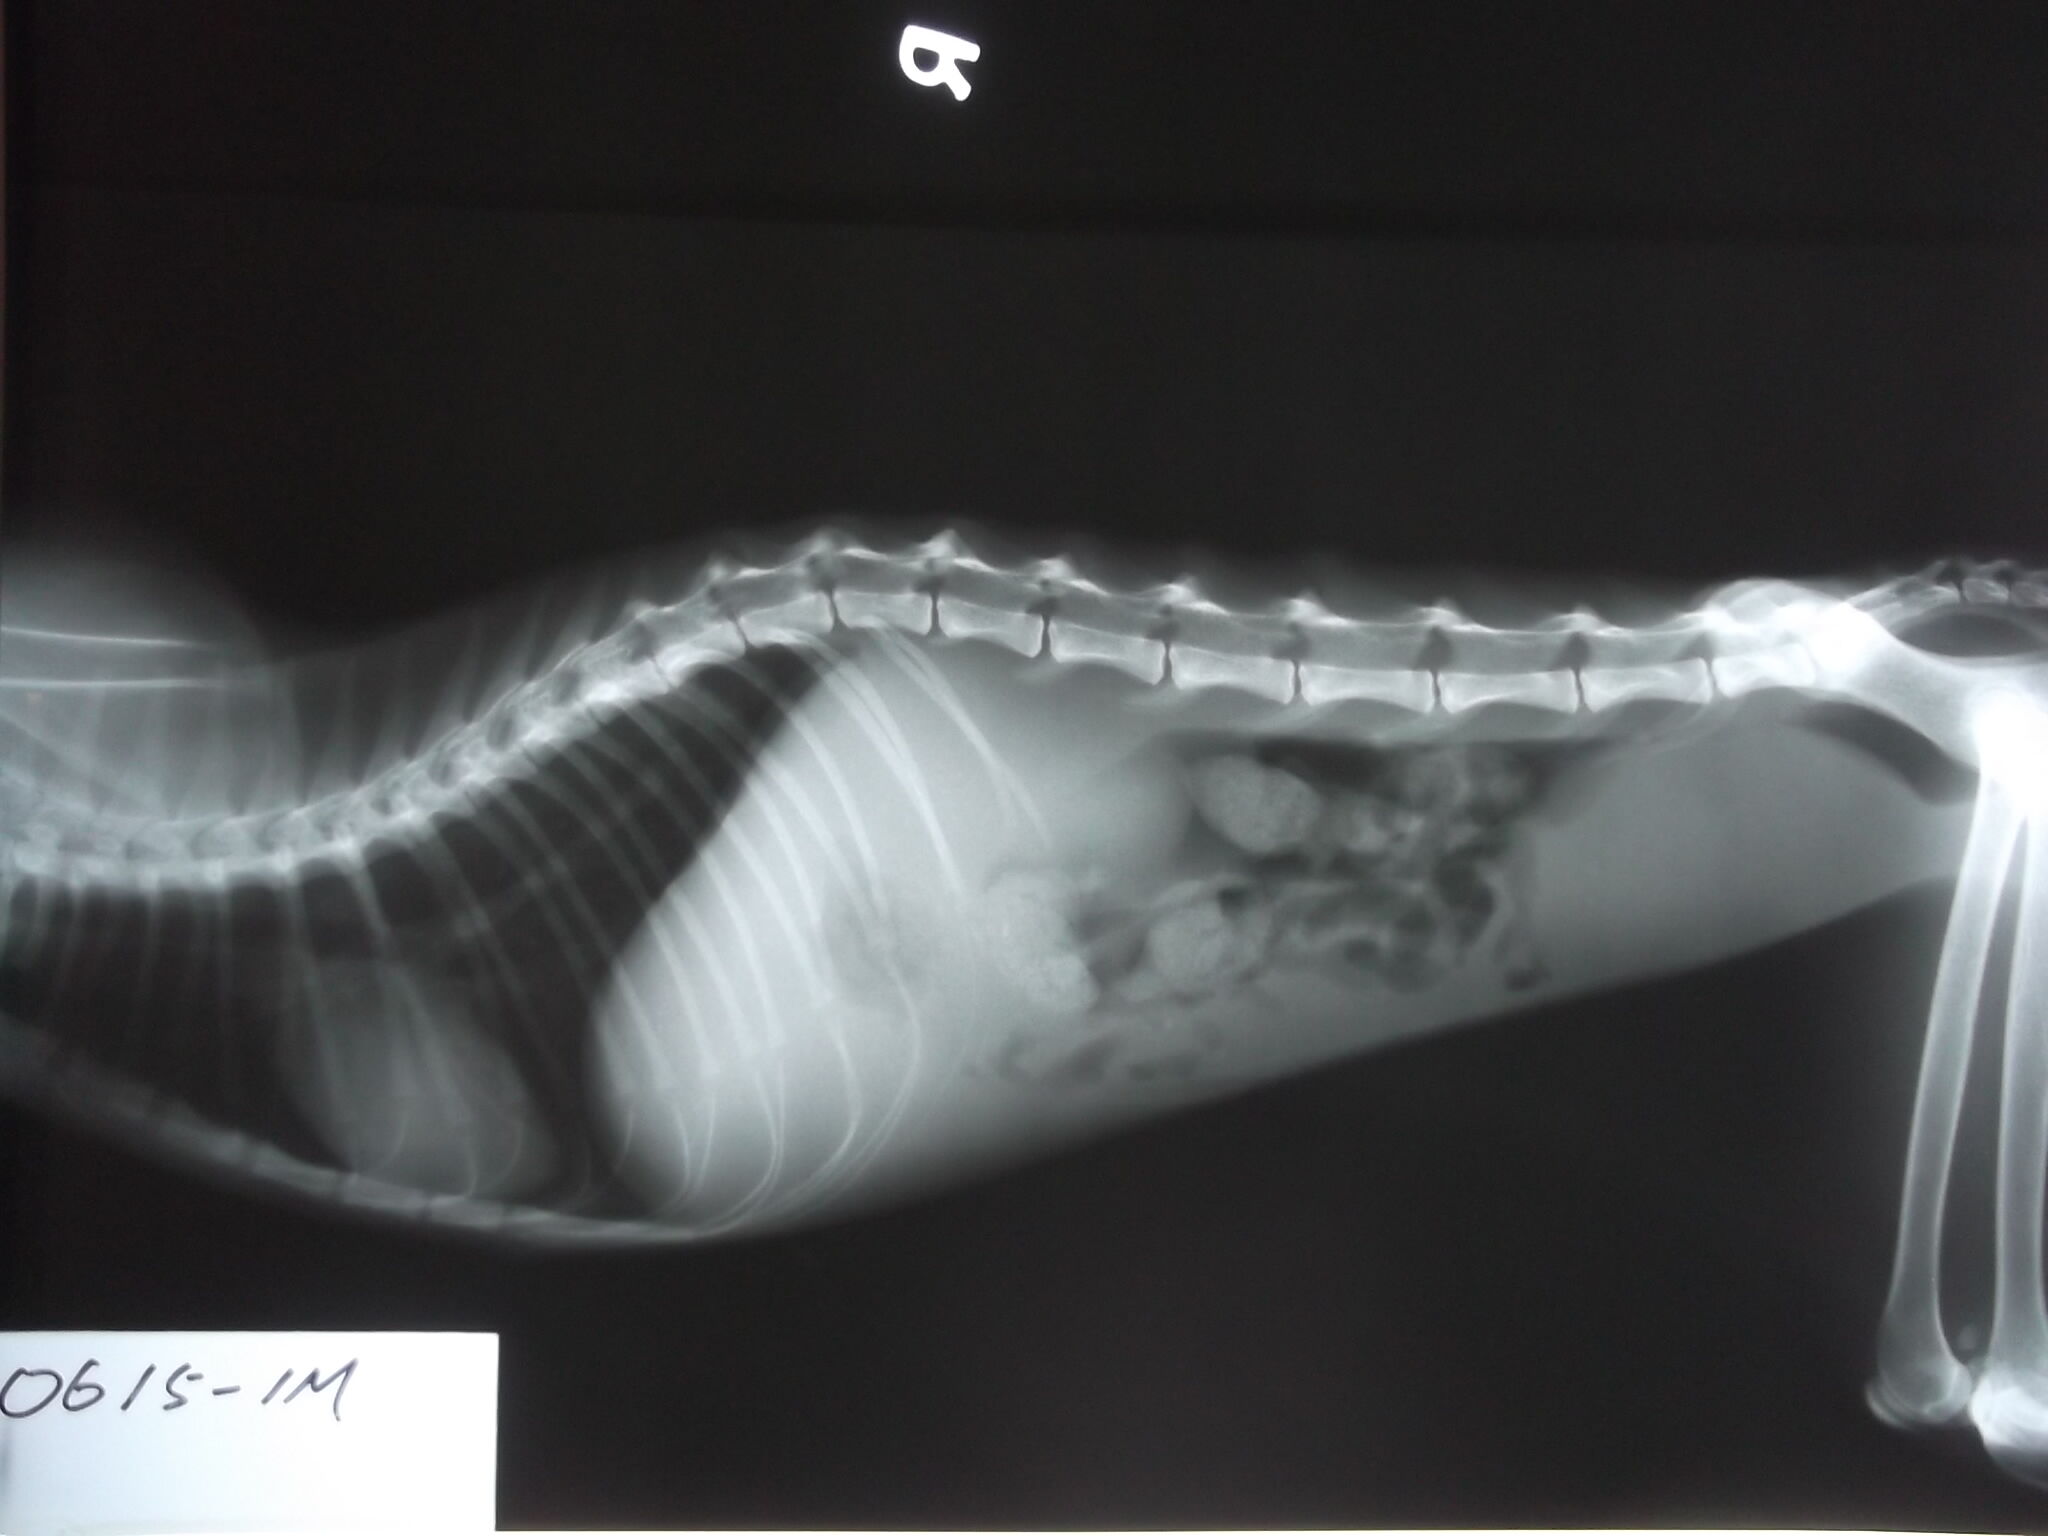

X光片下呈現腹水情形

5.X光 300*2=600

6.點滴(6/15~6/30) 300*15=4500

7.住院(6/15~7/10) 300*25=7500